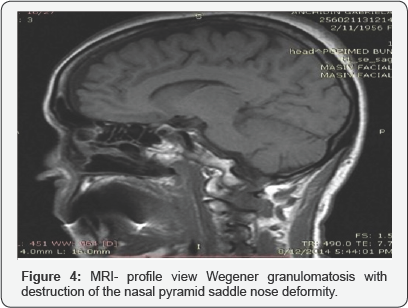

Involvement of the salivary glands is rare in Wegener granulomatosis (WG). It typically occurs early in the course of the disease, with enlargement of the parotids or sub maxillary glands. Extensive involvement of the salivary glands may produce sufficient destruction to simulate Sjogreen syndrome Figure 4.

nasal obstruction, purulent discharge, epitasis, crusting are the most frequent -hyposmia, reduction in the sense of smell, cacosmia may appear as a result of purulent secretions associated with growth of bacteria's such as Pseudomonas aeruginosa or Staphylococcus aureus, anemia in severe destructions ,collapse of the nose. Epiphora, other initial sign is caused by involvement of the nasolacrimal duct. Whistling symptoms in perforation of the nasal septum and in the more advanced cases "saddle nose" deformity. Perforations of nasal septum and their expansion can cause collapse of the cartilaginous part of the nose, which results in depressed appearance of the nose, so-called saddle- nose deformity. It deteriorates nasal obstruction and can cause anemia.